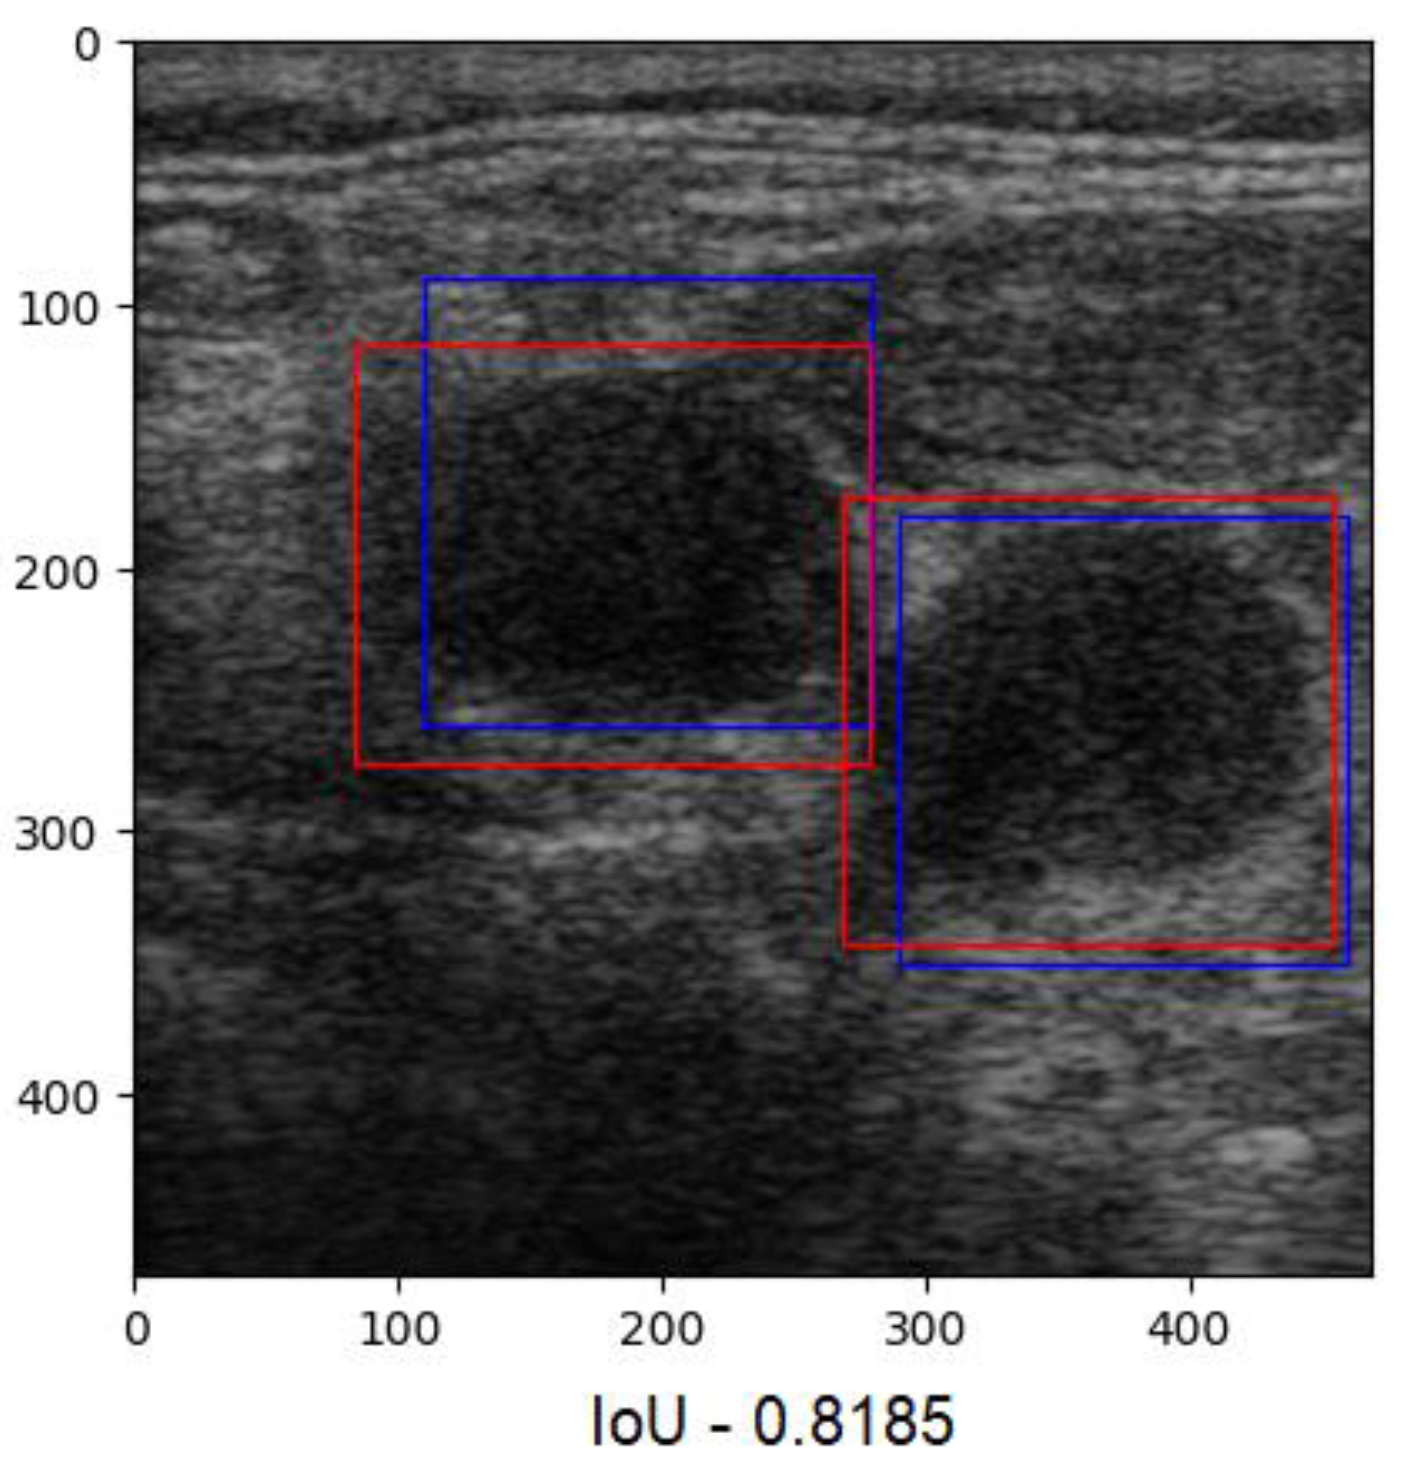

Since our goal was to determine the overlap ratio between the predictions and the labels made by the experts in the field, we searched for alternative ways of reaching our objective, so we applied another metric, IoU. The formula used to calculate IoU is presented in Equation (4) [23]. The better the alignment between the predictions and the label, the more accurate the network. Since this technique verifies each label individually, we averaged the results into a boxplot (Figure 9). The overlap ratio between the predictions and labels ranged between 47% and 84% on the test images, with an average of 74%. Few aberrant labels were ignored. One of the final predictions can be seen in Figure 10.

Figure 10. Predictions with an IoU overlap of 81%.